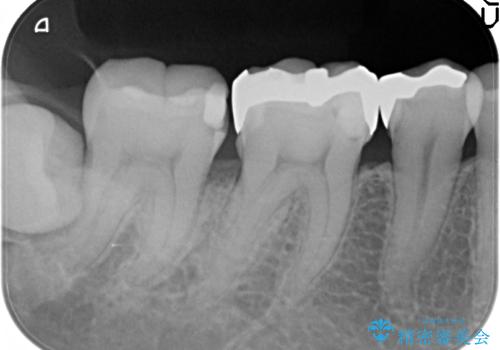

- 右下の奥の歯と歯の間に食べ物がつまること、つまったものがなかなか取れないことを主訴に来院されました。

右下6,7間に隙間があり、つめものの境目から虫歯になっていました。

セラミック希望とのことで、手前の歯も一緒に金属を外してセラミックにて修復することになりました。